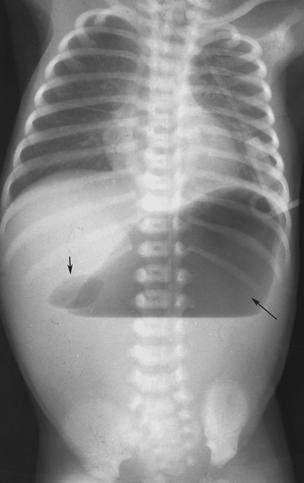

Abdominal radiography may be used to search for dilated small bowel and an absence of gas in the region of the cecum (see the image below). Presence of a hyperechoic core, representing mesenteric fat; This signifies peritoneal fat around the intussusception; 1) target sign, 2) crescent sign, … This target is usually ≥3 cm in diameter.

Plain abdominal xray of patient is done in supine and upright position. From the department of radiology, umass memorial, university of massachusetts, 55 lake ave north, worcester, ma 01655 (y.h.k., k.a.a.); Jan 10, 2022 · target sign (also known as the doughnut sign) pseudokidney sign; Some ultrasound features favor ileocolic over small bowel intussusception 14: Plain abdominal radiograph shows the target sign in the right upper quadrant abdomen. Plain abdominal radiograph shows the target sign in the right upper quadrant abdomen. Feb 01, 2022 · the target sign of intestinal intussusception, also known as the doughnut sign or bull's eye sign. Feb 23, 2022 · jan 10, 2022 · gastric intussusception: Feb 03, 2022 · to summarize, the radiographic signs of intussusception are: Xrays cannot be used to exclude intussusception in patients where suspicion of intussusception is very high. Crescent sign a soft tissue density projecting into the gas of the large bowel; Plain abdominal xray of patient is done in supine and upright position. A study shows target sign is present in 26% of patients;

The echogenic bands are formed by mucosa and muscularis whereas the submucosa is responsible fo the hypoechoic bands. To summarize, the radiographic signs of intussusception are: Xrays cannot be used to exclude intussusception in patients where suspicion of intussusception is very high. 1) target sign, 2) crescent sign, 3) absent liver edge sign (also called absence of the subhepatic angle), and 4) a bowel obstruction. Plain abdominal xray of patient is done in supine and upright position. Plain abdominal radiograph shows the target sign in the right upper quadrant abdomen. This signifies peritoneal fat around the intussusception; Crescent in a doughnut sign;

1) target sign, 2) crescent sign, 3) absent liver edge sign (also called absence of the subhepatic angle), and 4) a bowel obstruction. Jul 09, 2021 · the target sign of intestinal intussusception, also known as the doughnut sign or bull's eye sign. To summarize, the radiographic signs of intussusception are: The classic imaging findings include a "target sign" or "bull's eye" that occurs due to the layers of intestines within one another. This target is usually ≥3 cm in diameter. Mar 02, 2018 · the doughnut sign or target sign refers to the alternating echogenic (mucosa and muscularis)) and hypoechoic (submucosa) concentric bands which are caused by the invagination of the bowel produce_48 if you look carefully at this clip you can see the classic "doughnut" or target sign of intussusception. Plain abdominal radiograph shows the target sign in the right upper quadrant abdomen. Abdominal ultrasound is the modality of choice, with sensitivity and specificity approaching 100% when performed by experienced ultrasonographers. 1) target sign, 2) crescent sign, … Plain abdominal xray of patient is done in supine and upright position. Jul 09, 2021 · the target sign of intestinal intussusception, also known as the doughnut sign or bull's eye sign. Abdominal radiography may be used to search for dilated small bowel and an absence of gas in the region of the cecum (see the image below). Xrays cannot be used to exclude intussusception in patients where suspicion of intussusception is very high.

To summarize, the radiographic signs of intussusception are: Crescent sign a soft tissue density projecting into the gas of the large bowel; Plain abdominal xray of patient is done in supine and upright position. This signifies peritoneal fat around the intussusception; Abdominal ultrasound is the modality of choice, with sensitivity and specificity approaching 100% when performed by experienced ultrasonographers. Recall that the target sign is a mass in the right upper quadrant. Xrays cannot be used to exclude intussusception in patients where suspicion of intussusception is very high. To summarize, the radiographic signs of intussusception are:

The target sign of intestinal intussusception, also known as. Plain abdominal radiograph shows the target sign in the right upper quadrant abdomen. A study shows target sign is present in 26% of patients; Feb 03, 2022 · to summarize, the radiographic signs of intussusception are: Recall that the target sign is a mass in the right upper quadrant. Larger anteroposterior diameter (mean 2.6 cm vs. To summarize, the radiographic signs of intussusception are: This target is usually ≥3 cm in diameter. Feb 07, 2022 · the target sign of intestinal intussusception, also known as the doughnut sign or bull's eye sign. Presence of a hyperechoic core, representing mesenteric fat; Feb 23, 2022 · jan 10, 2022 · gastric intussusception: To summarize, the radiographic signs of intussusception are: Xrays cannot be used to exclude intussusception in patients where suspicion of intussusception is very high.